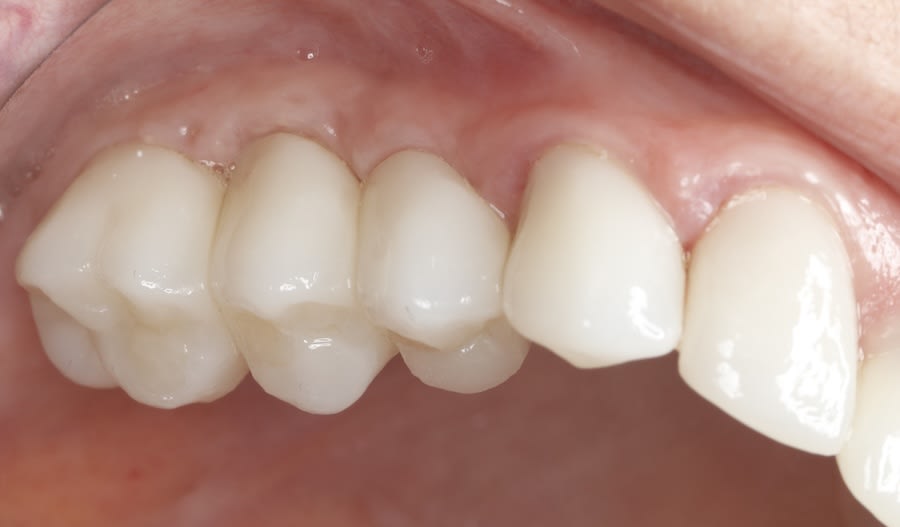

Case 1 (Figure 3 through Figure 24) depicts a 3-year follow-up of combined osseodensification sinus protocol IV in a severely resorbed maxillary ridge with ≤0.5 mm bone height in molar sites and horizontal deficiency at the first premolar site, using a two-stage approach for implant placement.